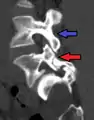

Anterolisthesis L5/S1. Blue arrow normal pars interarticularis. Red arrow is a break in pars interarticularis.

Anterolisthesis L5/S1

Magnetic Resonance Imaging (MRI)

Magnetic resonance imaging is the preferred advanced imaging technique for evaluation of spondylolisthesis.[30] Preference is due to effectiveness, lack of radiation exposure, and ability to evaluate for soft tissue abnormalities and spinal canal involvement.[30][31] MRI is limited in its ability to evaluate fractures in great detail, compared to other advanced imaging modalities.[32]